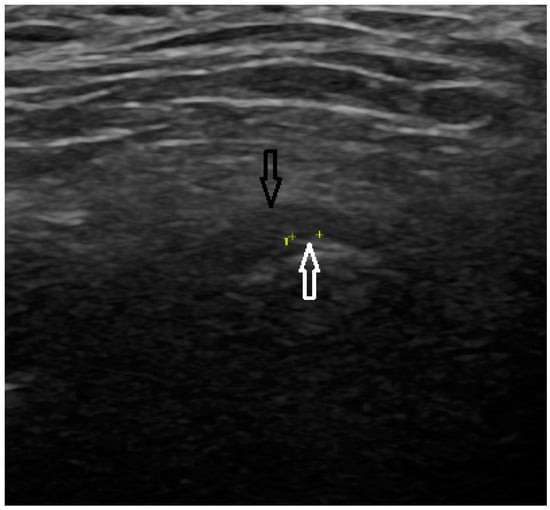

All MRI examinations were performed using a 3T MRI scanner (MAGNETOM Vida, Siemens AG, Erlangen, Germany) with a dedicated head coil. A special protocol (Table 1 consisting of three scanning phases was prepared for the study: 1. mouth closed, 2. mouth opening 2 cm (a dilator was used), 3. mouth maximally opened. In the MRI examination, a detailed analysis was performed on the TM joint structures. The presence of osteophytes and erosive changes to the bone surfaces were also assessed, as these can indicate progressive joint damage and contribute to the severity of the condition. Additionally, the condition of the articular disc was examined for any signs of displacement or degeneration, while the presence of synovial effusion was evaluated to determine the extent of joint inflammation and fluid accumulation (Figure 4).

Figure 4. PD TSE SPAIR Sagittal MRI scan (articular disc—white arrow).